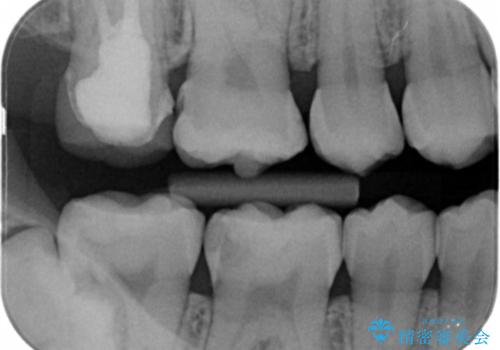

- 右下大臼歯の保険材料劣化に伴う虫歯の治療を希望された患者さまです。

審美性や精度の高い治療を希望されたので切削量や形態を考慮し、セラミックインレーでの治療を選択しました。

保険治療で使用される材料は劣化しやすく直下で虫歯が進行していることが多いです。

今回の患者さまは遠心部の虫歯が深かったのでCRで裏層した上で形成・印象を行いインレーセットを行っています。